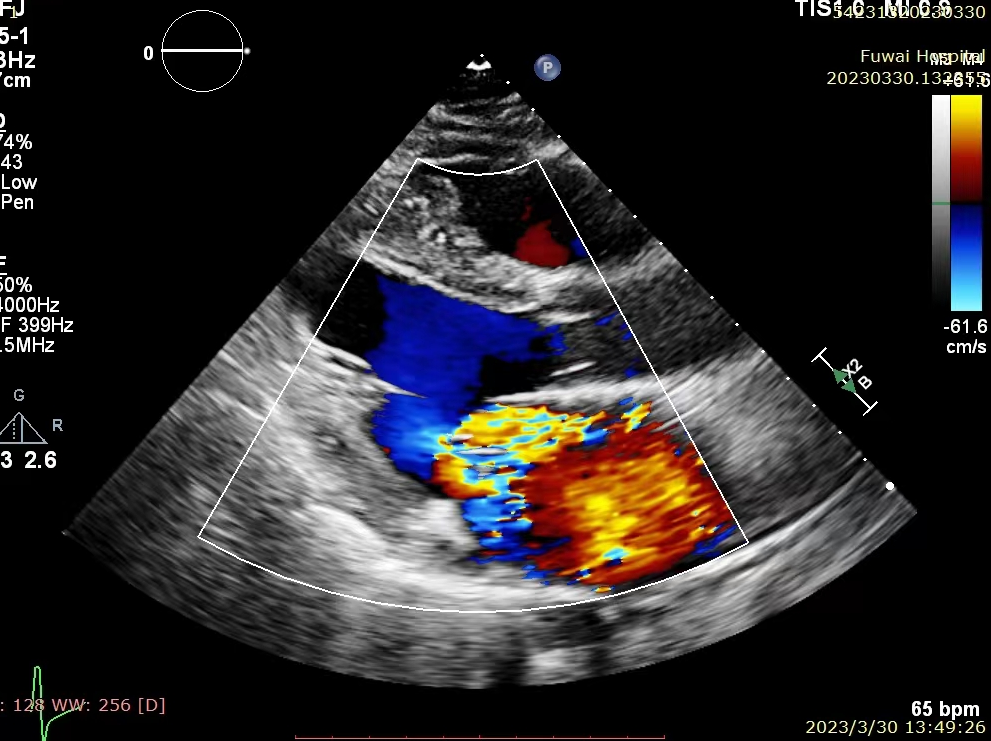

患者为高龄男性,年龄82岁。术前超声心动图诊断为重度退行性二尖瓣反流(MR 4+),反流位于2区,后叶P2区脱垂合并腱索断裂,多普勒检查可见大量偏心性反流。心脏团队评估该患者为外科高风险患者,考虑使用MitraClip™进行经导管二尖瓣缘对缘治疗,因患者有食道狭窄病史,经术前讨论评估,决定为该患者行单纯经胸超声(TTE)引导下MitraClip™手术。

患者术前超声

术后即刻超声图